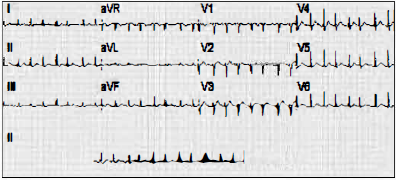

Paciente de 56 anos de idade deu entrada na emergência com quadro de palpitação e síncope. Ao realizar exame físico, sua pressão arterial era de 80 x 60 mmHg e sua frequência cardíaca era de 160 bpm. Realizou o ECG abaixo logo que adentrou a emergência.

O diagnóstico e o tratamento desse paciente são, respectivamente: